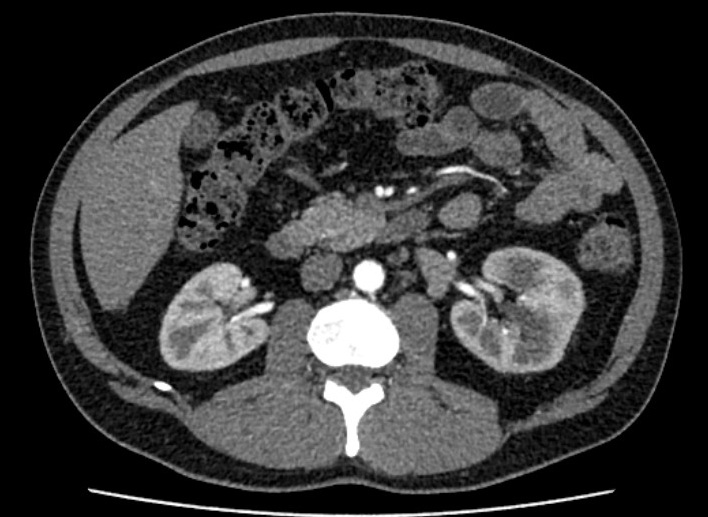

Computertomographie axiales Schnittbild der Nieren

Die Computertomographie ist ein modernes bildgebendes und absolut schmerzfreies Schnittbildverfahren, bei dem mithilfe von Röntgenstrahlen unterschiedliche Körperregionen dargestellt werden.

Unser hochmodernes Gerät (Aquillion Prime SP) weist neben einer sehr hohen Bildqualität auch eine stark verminderte Strahlenbelastung auf.